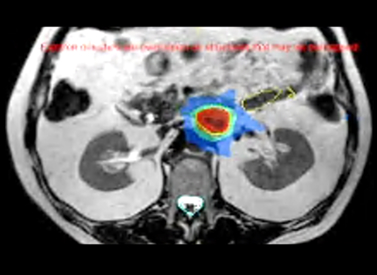

MR-guided SBRT for small adrenal gland metastases

Certainty to deliver SBRT to small soft tissue targets accurately and efficiently with 2 mm margins

Accounting for motion whilst delivering the beam is made possible by True Tracking. It continuously tracks the 3D position of any target non-invasively and in real-time. Four strategies can be used for rapid beam gating.

The tracking algorithm enables the prediction of what the tumor will do next. This combined with low system latency gives confidence that the beam is turning on and off when expected.